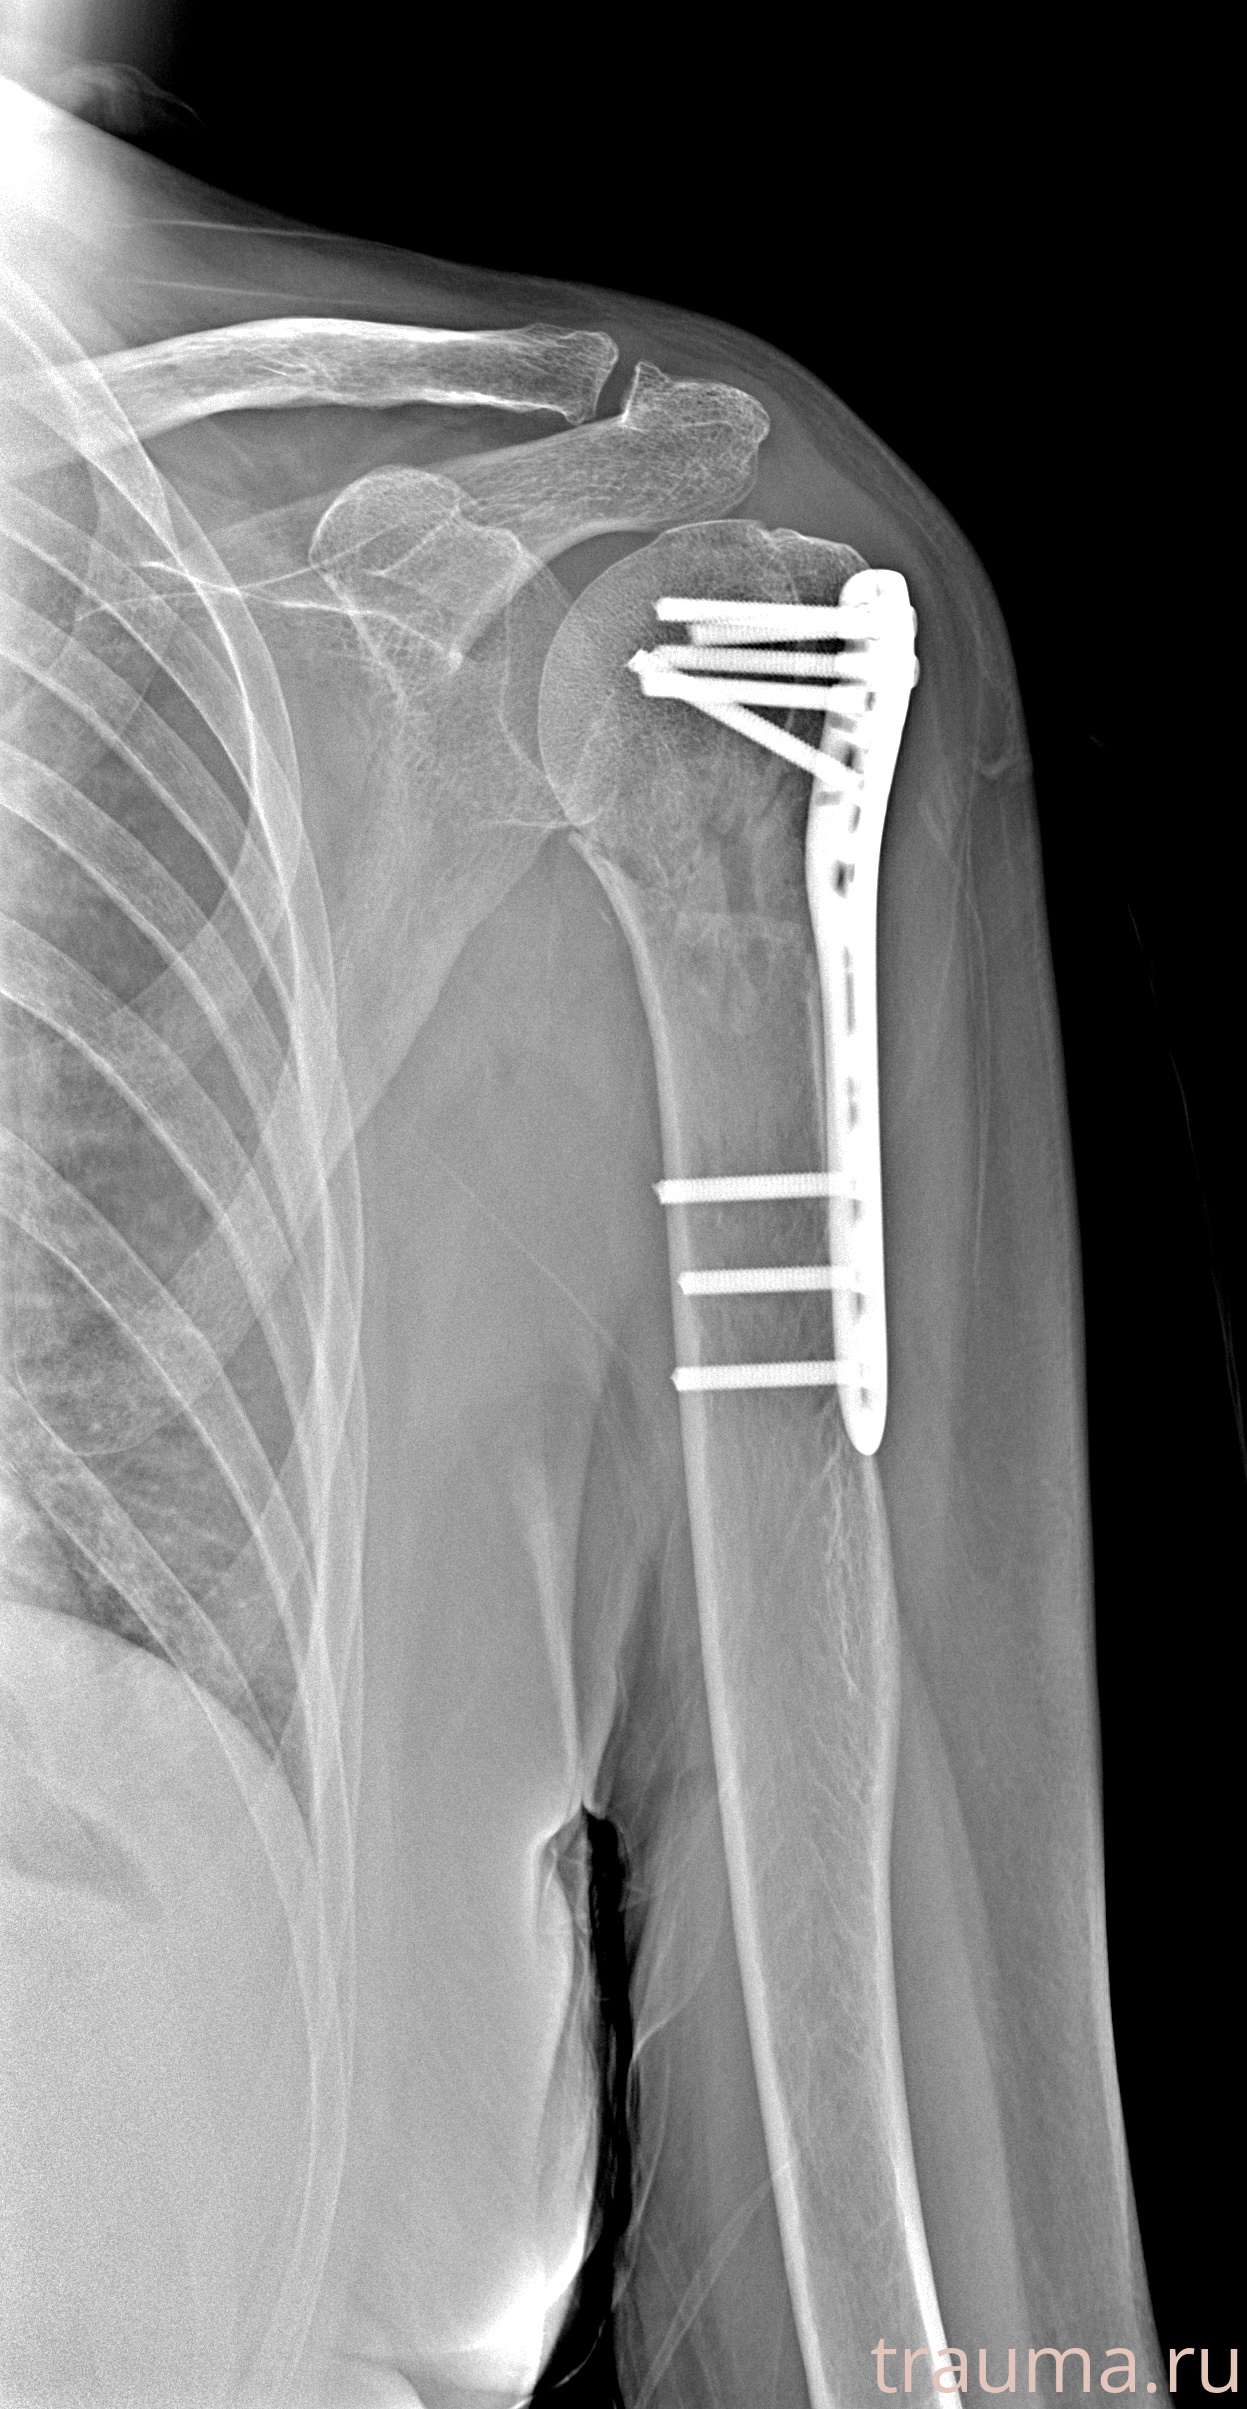

Рентгенограммы